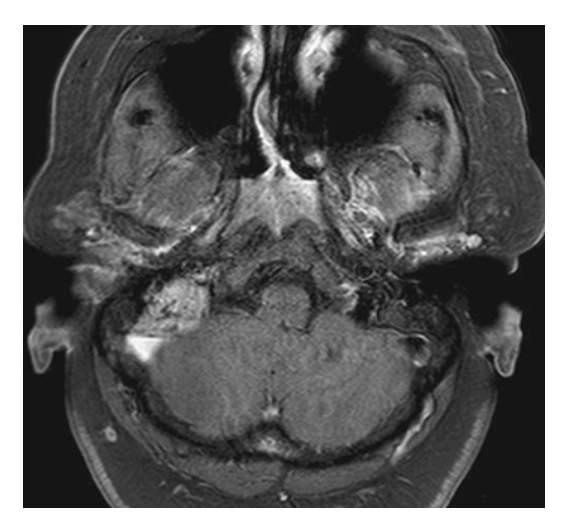

What does the figure show?

Glomus Tumor (Glomus Jugulotympanicum). Axial fat-sat (FS) T1W with gadolinium shows enhancing mass in right mastoid region and jugular fossa. Serpentine flow voids represent vessels.

Glomus Tumor (Glomus Jugulotympanicum). Coronal FS T1W with gadolinium shows enhancing mass extending from right middle ear into jugular fossa representing a glomus jugulotympanicum tumor (paraganglioma).